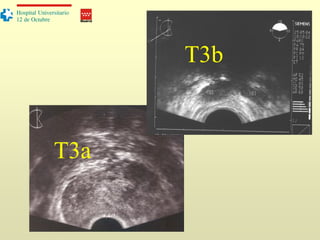

Estadificación

T2: tumor localizado dentro de la próstata

T3a: Tumor que afecta la cápsula

T3b: Invasión de vesículas seminales

T4: invasión de órganos adyacentes (recto, vejiga…)

T2

T3a

T3b